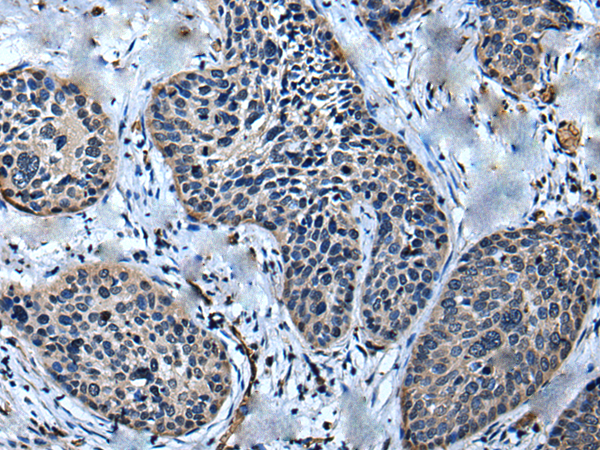

分类: 科研抗体货号: P02350别名: HSPC155应用: WB,IHC反应种属: Human, Mouse, Rat